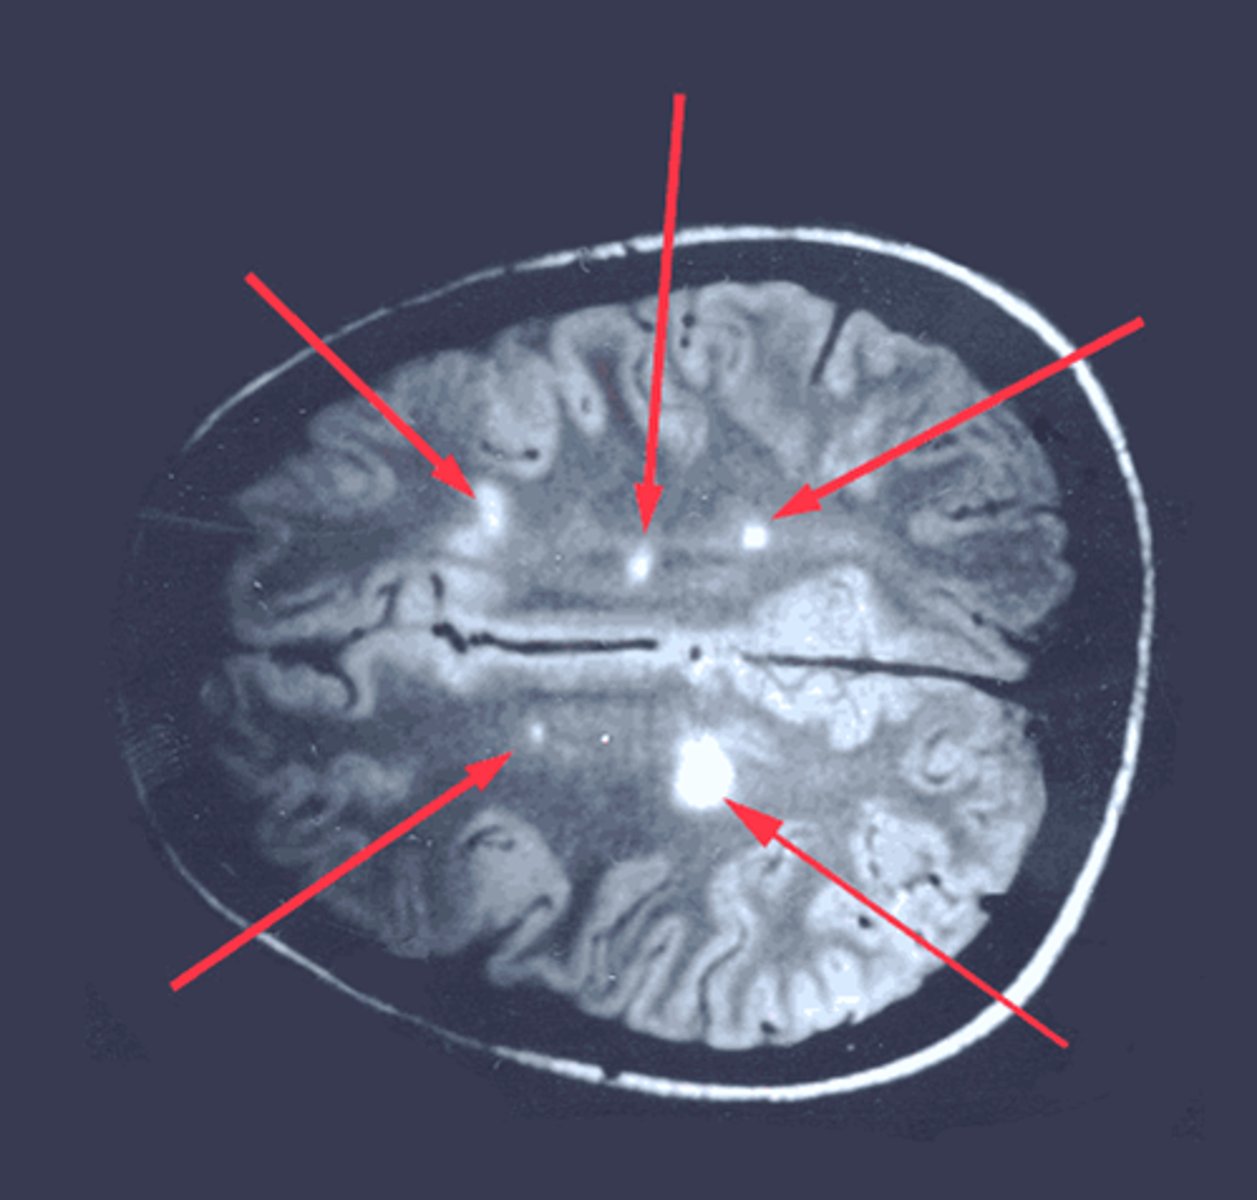

Multiple sclerosis

Type IV hypersensitivity

Dx: Oligoclonal IgG bands and periventricular plaques on MRI